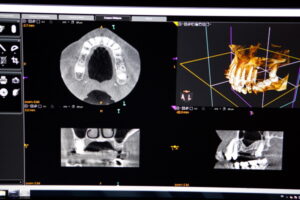

精密な診査・診断

Jaw scanner prescribed for dental implant placement.